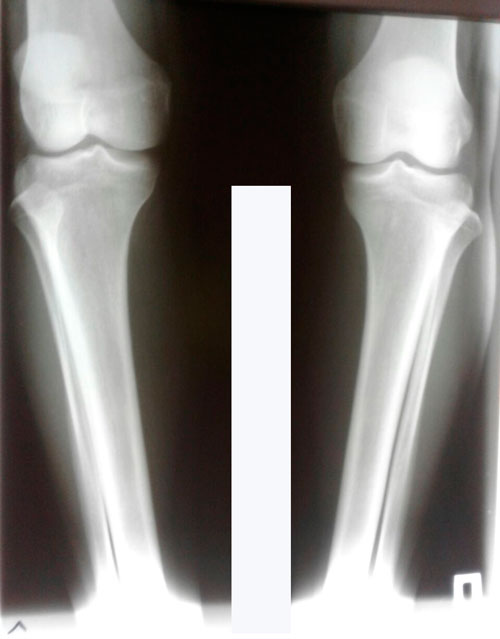

Исходник 28 лет.

Дата операции 17.03.2018г.

Вложения

IMG-20180316-WA0026.jpg

IMG-20180316-WA0029.jpg